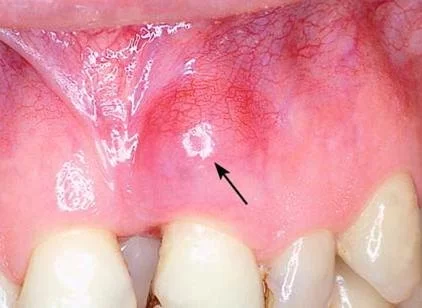

One of the first warning signs of tooth abscess infection is persistent toothache. Unlike normal sensitivity, the pain is deep, sharp, and often radiates to the jaw, neck, or ear. Swelling of the face or gums, bad taste in the mouth, and difficulty chewing are also common indicators. In some cases, people report that their gums feel unusually tender or that a small bump appears near the infected tooth. These early symptoms are often underestimated, but they are red flags of a progressing dental issue.

2.1 Differences Between Mild and Severe Pain

While a cavity may cause discomfort only when eating sweets or drinking cold beverages, an abscess creates lingering pain that doesn’t subside easily. This constant discomfort signals that bacteria have already penetrated deep layers of the tooth or gum tissue. Identifying this distinction early can prevent costly treatments later.